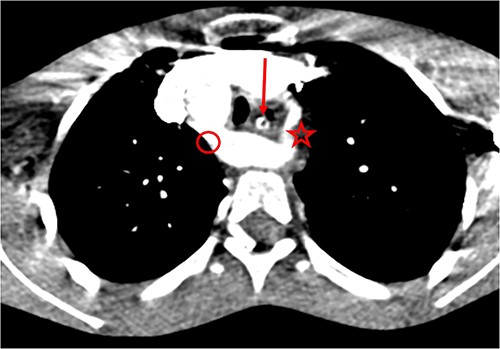

Post-operative medical treatment consisted of a nasogastric feeding tube, parenteral administration of omeprazole (40 mg/day), and amoxicillin/clavulanic acid (02 g/day in two doses) for 10 days. On postoperative Day 6, the patient presented with profuse haematemesis, requiring macromolecular infusion and transfusion of packed red blood cells. A thoracic angio-CT scan was performed the following day and revealed the same lesions as on the CT scan, with no images suggestive of aneurysms or oesovascular fistulas (Fig. 3). Omeprazole (20 mg/day) per os was continued for 6 weeks, and meal splitting was advised. The patient was subsequently lost to follow-up, but telephone contact revealed that there had been no recurrence of bleeding at 2 years’ follow-up.

Double aortic arch on thoracic angio-CT scan: arrow (esophagus), star (left arch), circle (right arch).